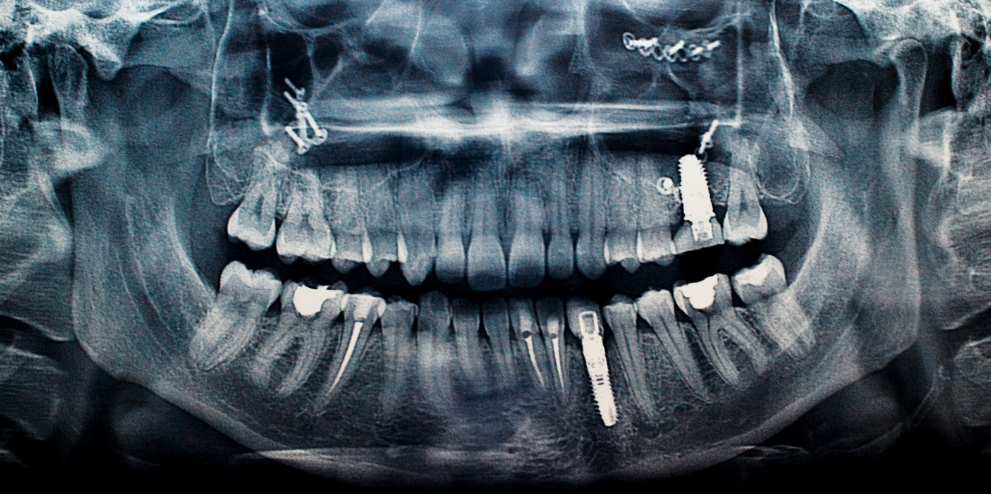

임플란트는 치아를 상실했을 때 자연치아를 대체할 수 있는 효과적인 방법 중 하나입니다. 하지만 많은 사람들이 임플란트 가격, 시술 과정, 유지 관리법 등에 대해 궁금해합니다.

임플란트 시술 과정

임플란트 시술은 보통 다음과 같은 단계로 진행됩니다.

1️⃣ 인공치근(픽스처) 식립 – 티타늄/세라믹 픽스처를 잇몸뼈에 심는 과정

2️⃣ 지대주(어버트먼트) 연결 – 픽스처가 턱뼈와 결합된 후 보철물 연결을 위한 부품 장착

3️⃣ 보철물(크라운) 장착 – 최종적으로 치아 역할을 하는 보철물을 장착하여 완성

⏳ 이 과정은 최소 3~6개월이 소요되며, 잇몸뼈 상태에 따라 더 길어질 수도 있습니다.